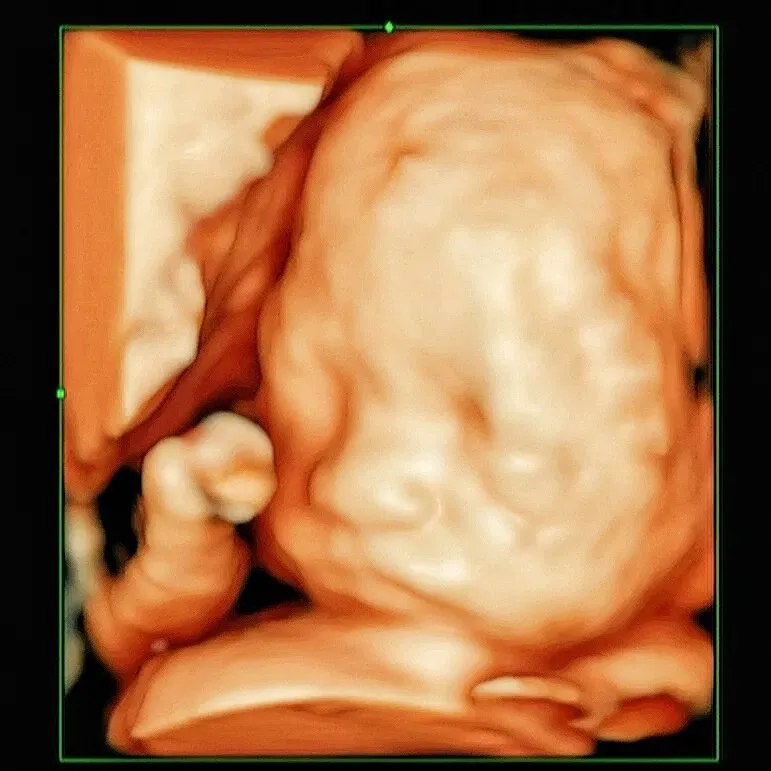

通俗来说:二维看结构,三维看静态样貌,四维看动态画面,而5D高清四维彩超,是搭载AI智能系统的全新一代超声黑科技,依托AI智能图像优化技术,降噪、增强细节、提亮对比度,一扫传统超声的模糊、噪点问题。就像给B超装了专业镜头,宝宝的小脸蛋、小拳头、甚至睫毛纹理都能清晰捕捉,每一帧都能截出绝美“宫内写真”。

不用再等出生!5D高清能清晰看到宝宝的一举一动:揉眼睛、吐舌头、打哈欠、蹬小腿,甚至还能捕捉宝宝微笑的小表情。